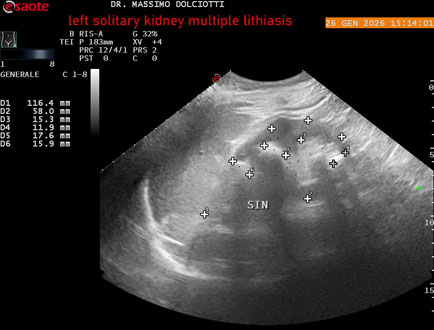

Data inserimento: 29/01/2026

Ecografia del: 26/01/2025

Strumento: Esaote MyLab Eight

Sonda: Conevx Multifrequenza 1-8 MHz

Età Paziente: M 78 anni

Motivazione dell'esame: follow up di litiasi al rene sinistro, in paziente sottoposto a nefrectomia destra.

Commento all'esame: le immagini ed il video documentano il rene sinistro in sede, di ecostruttura disomogenea per evidenza di multiple formazioni litiasiche al pielone superiore, delle dimensioni di 15,9 mm, al pielone medio di 17,5 mm e al pielone inferiore di 18,9 mm e morfovolumetria normale, con diametro bipolare di 115 (v.n. 90-120 mm) x 54 mm e parenchima renale dello spessore di 17 mm ( v.n. > 13 mm).

Conclusioni: litiasi multipla del monorene sinistro (multiple lithiasis of the left solitary kidney).